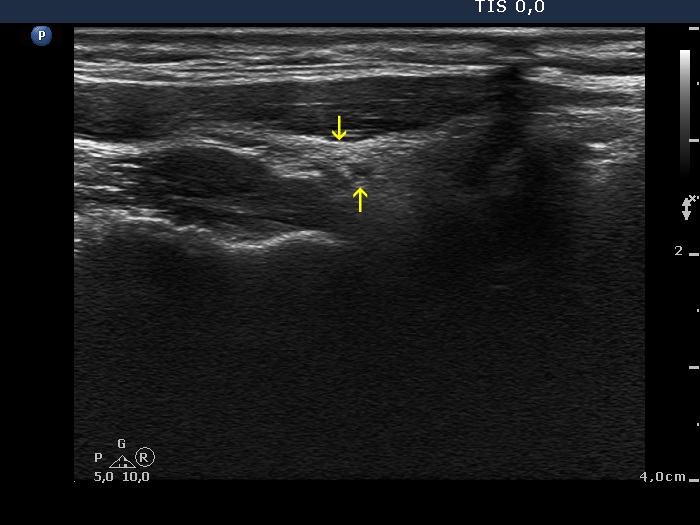

Right lobe, longitudinal scan

Right lobe, longitudinal view. Yellow arrows point to the tiny hypoechoic areas.